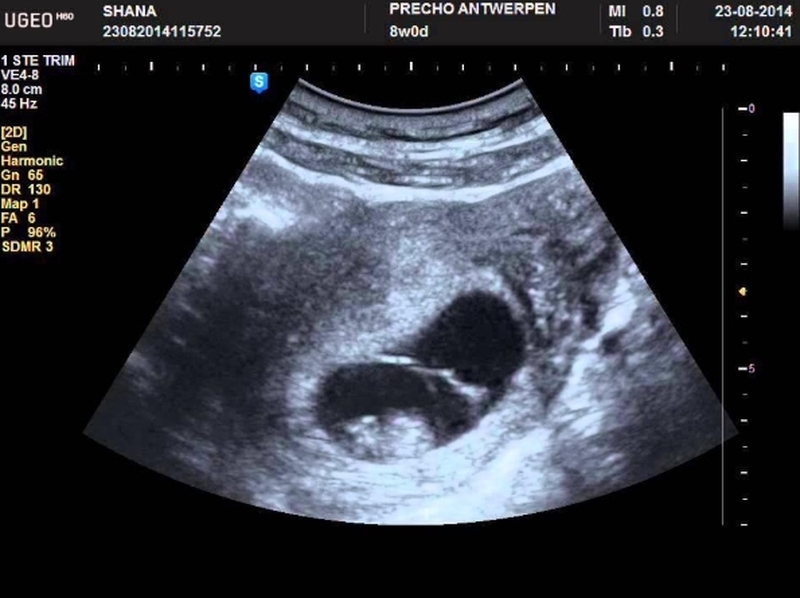

Thực chất thì việc phát hiện phôi thai hay tim thai thông qua siêu âm không phụ thuộc hoàn toàn vào tình trạng sức khỏe của người mẹ hay sự hình thành, phát triển của thai nhi. Về cơ bản thì đến tuần thứ 7 của thai kỳ, phôi thai sẽ xuất hiện với kích thước khoảng 2mm sau đó theo thời gian nó sẽ to lớn hơn. Nhưng bên cạnh đó, có một số trường hợp khi mang thai đến tuần thứ 7 nhưng chỉ phát hiện có yolksac mà không thấy có phôi thai. Tình trạng này phụ thuộc bởi nhiều nguyên nhân có thể kể đến như: thai nhi phát triển chậm, tính nhầm tuổi thai, trứng bị trống...

Các mẹ bầu cũng cần phải chú ý đến vấn đề siêu âm khi có yolksac, bởi thường thì túi noãn hoàng chỉ dày từ 2 - 5mm, vậy nên nếu kích thước của túi noãn hoàng càng dày thì tỷ lệ hình thành phôi thai sẽ càng thấp. Điều này sẽ gây ra nguy hiểm đối với thai nhi và khả năng sảy thai sẽ cực kỳ cao. Chính vì thế, qua siêu âm mà phát hiện yolksac quá dày thì mẹ bầu cần nhờ đến sự hỗ trợ của bác sĩ để chăm sóc sức khỏe cũng như sử dụng các biện pháp can thiệp phù hợp để giữ lấy sự sống của thai nhi.